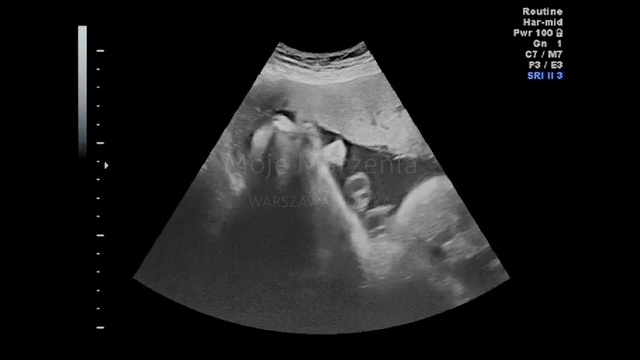

Best Video References: Infant ultrasound

Featured videos selected by a smart neural network algorithm